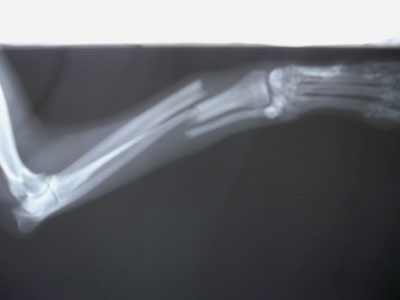

Πιντσεράκι 5,5 kg με 5ημερών τέλειο κάταγμα κάτω τρίτου διάφυσης αριστερής κερκίδας και ωλένης.